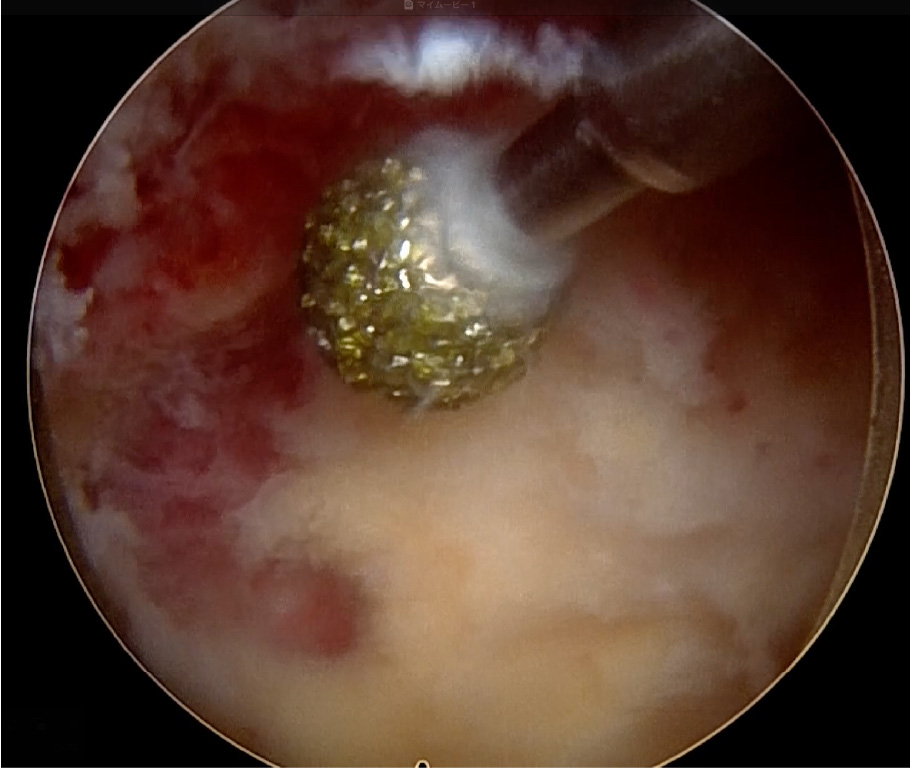

術中写真: